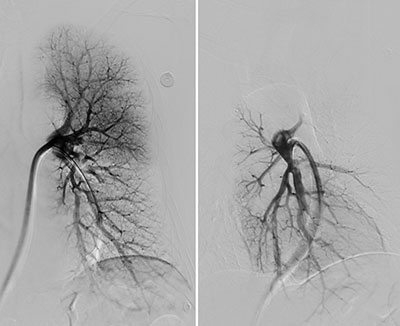

手术采用局麻的方式,经皮穿刺右股静脉,进入肺动脉造影后进一步明确诊断,左肺大面积肺栓塞。将鞘管到达左肺动脉后,应用Tendvia装置给予取栓,取出大量混合性血栓,取栓后左肺动脉血流完全恢复,血流分级达到Grade Ⅰ级,患者胸闷立即缓解。

多角度造影示左肺血流恢复

为了预防再次肺栓塞的发生,科室同期行下腔静脉滤器植入术及左下肢Angiojet血栓清除术。应用肺动脉取栓的同一入路,右侧股静脉放置滤器后,翻山至左下肢静脉,造影明确左下肢混合性血栓,由肌间静脉延伸至髂静脉,经Angiojet吸栓后左下肢深静脉完全复通。

术前与术后左下肢静脉造影对比